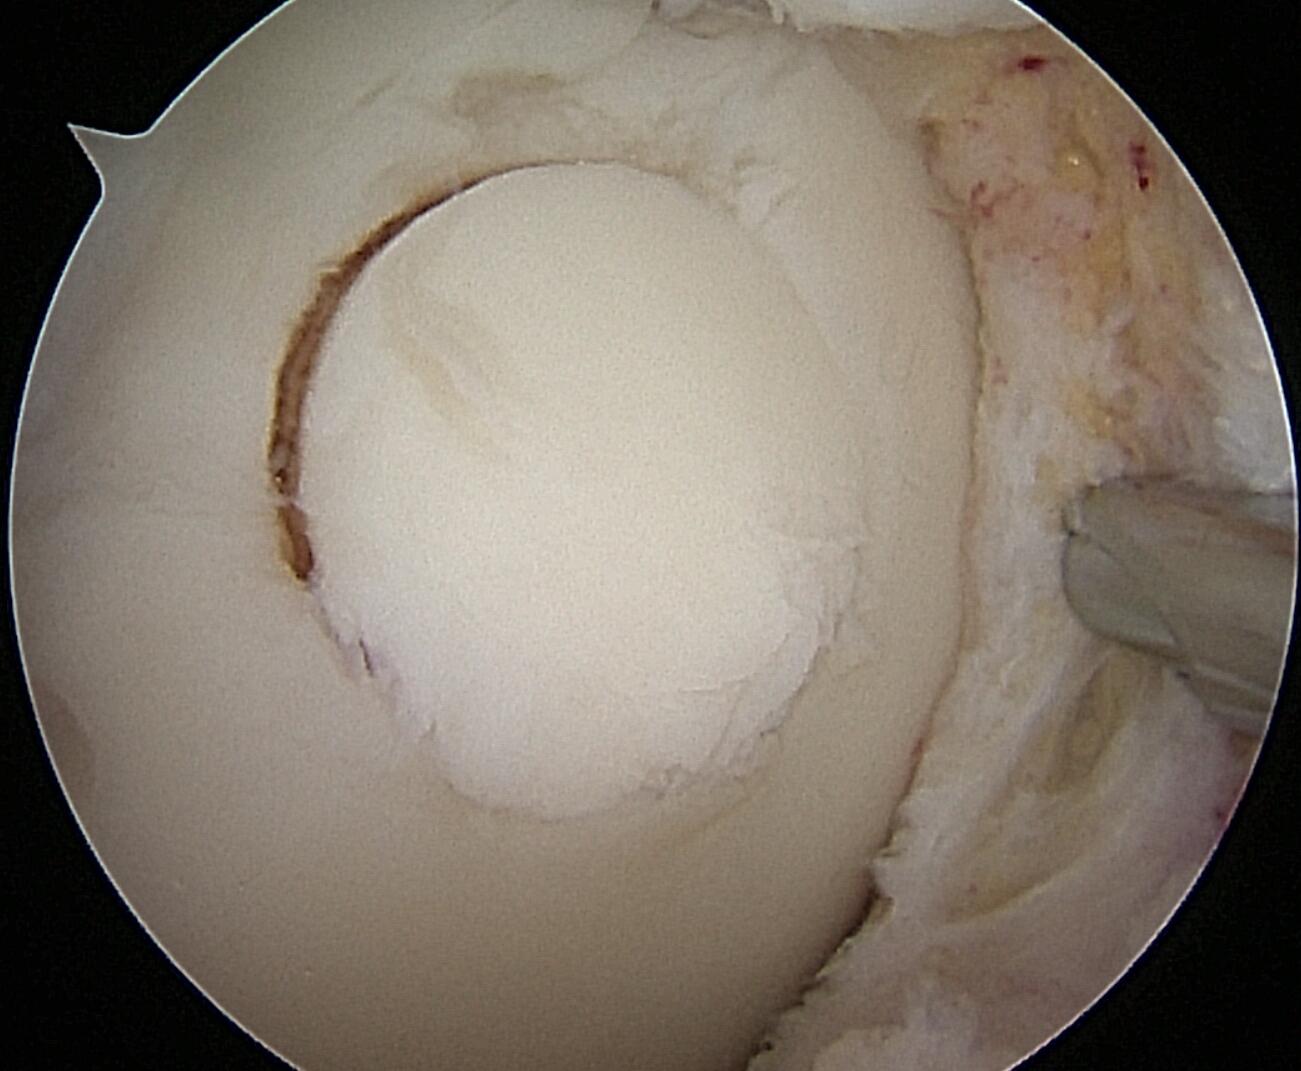

IntroducciónEl trasplante osteocondral autólogo es una alternativa quirúrgica en lesiones focales del cartílago articular. El objetivo de nuestro trabajo fue evaluar una serie de 62 pacientes tratados con mosaicoplastía de rodilla con 8 años promedio de seguimiento.Material y métodosEvaluamos retrospectivamente 62 pacientes operados con mosaicoplastía entre el año 2001 y 2014. Se incluyeron pacientes con lesión de cartílago focal de la rodilla a los que se les realizó mosaicoplastía aislada o asociada a otros procedimientos quirúrgicos (reconstrucción de LCA, osteotomía). Con un seguimiento mínimo de 2 años. Se evaluaron con las escalas de Lysholm e IKDC y el grado de artrosis con la escala radiográfica de Kellgren-Lawrence.ResultadosCuarenta y cinco fueron hombres y 17 mujeres. La edad promedio fue de 36 años. Treinta y cinco en cóndilo interno, 12 cóndilo externo, 12 tróclea y 3 combinadas. Cuarenta y dos fueron mosaicoplastías aisladas y 20 asociados a otro procedimiento. El resultado promedio de la escala de Lysholm al momento de la evaluación fue 80.1 y el IKDC fue 66.7. No encontramos diferencias significativas en la escala de Lysholm e IKDC entre los grupos de mosaicoplastía aislada y asociada a otro procedimiento. En 30 pacientes evaluados con radiografía se observó una inclusión satisfactoria del taco óseo.ConclusionesDentro de las opciones quirúrgicas se encuentran las microfracturas, el auto/alo injerto osteocondral y el implante de condrocitos autólogos. Todas estas técnicas han demostrado mejorar el estado clínico en comparación con el estado preoperatorio independientemente de cuál se utilice. En nuestra serie de pacientes operados con mosaicoplastía encontramos resultados satisfactorios en las evaluaciones clínicas.Consideramos que la mosaicoplastía es un procedimiento con alto grado de satisfacción y buenos resultados funcionales en pacientes con lesiones focales del cartílago articular. AbstractIntroduction: Osteochondral autograft transplantation is a surgical alternative for osteochondral defects of the knee. The aim of this study was to analyze a series of 62 patients treated with osteochondral autograft transplantation of the knee and an average follow-up of 8 years.Methods: A total of 62 patients treated with osteochondral autograft transplantation between 2001 and 2014 were evaluated. Patients with focal osteochondral lesions who underwent osteochondral autograft transplantation alone or associated with another procedure and a minimum follow-up of 2 years were included. Lysholm score, IKDC, and Kellgren- Lawrence radiographic scale were used. Forty-five men and 17 women (average age 36 years) were evaluated. Lesions were localized in medial condyle (35), lateral condyle (12), patella (12), and three were combined. Forty-two patients underwent isolated osteochondral autograft transplantation while 20 patients underwent associated surgical procedures.Results: Mean Lysholm score was 80.1 and IKDC score was 66.7. There were no significant differences in the Lysholm and IKDC scores between groups. Radiographic results demonstrated complete graft incorporation in 30 patients. Clinical evaluation revealed satisfactory results.Conclusion: Osteochondral autograft transplantation to treat osteochondral lesions is a procedure with a high clinical satisfaction and good functional results in patients with focal osteochondral lesions.Descargas